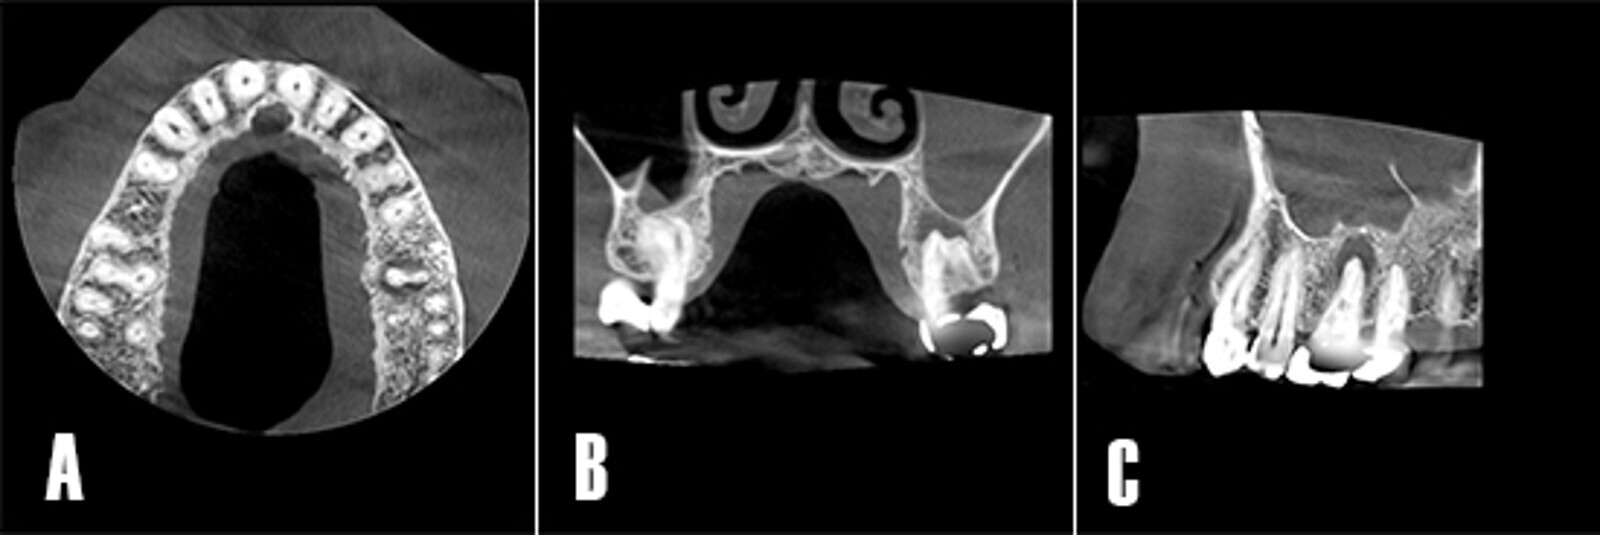

La sutura se removió una semana después de la cirugía. Se pudo observar como la tumefacción de los tejidos blandos remitió (Fig. 7A). El paciente fue citado 4 semanas tras la cirugía para monitorizar la sintomatología clínica y evaluar la zona tratada (Fig. 7B). A los 12 meses se reevaluó el caso (Fig. 7C) y se realizó una TCHC para valorar el seno maxilar afectado, se pudo observar como la cicatrización de la periodontitis apical y la patología sinusal remitieron (Fig. 8).

Figura 8. Control tomográfico a los 12 meses. A) Corte en el plano axial: se observa la cavidad sinusal sin opacificación. B) Corte coronal: se observa la cavidad sinusal limpia, la zona apical se observa más radiodensa, lo que sugiere la formación de hueso nuevo. C) Corte sagital: se aprecia cómo el engrosamiento de la membrana se asocia a la presencia del septo óseo del seno maxilar.